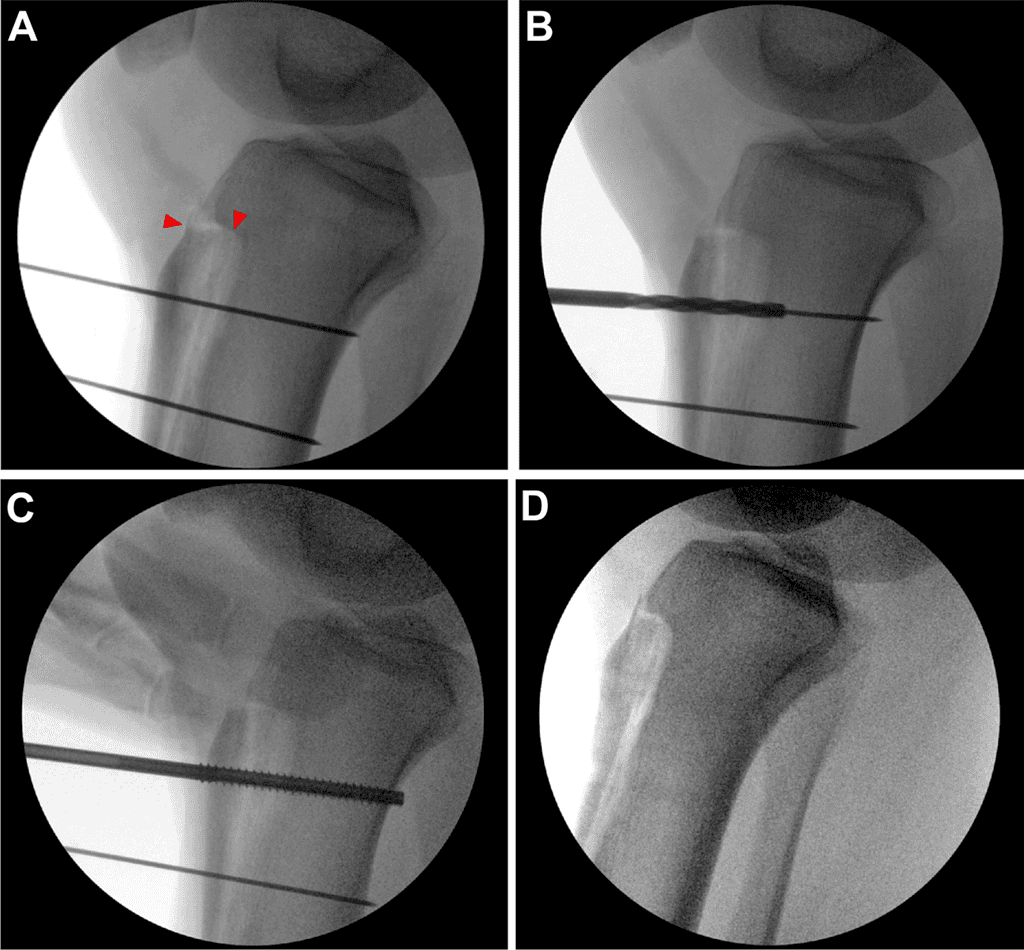

Sixty-two TTOs were analyzed (44 metal, 18 biointegrative). There were no exclusions and all were primary TTO. The overall cohort was 61.3% female, with median age of 23.3 years (interquartile range [IQR] 22.5 years) and BMI 25.7 (IQR 5.0). Because of limited numbers in each subgroup, further analysis remained aggregated by sex. Only 1 patient (1.6%) was an active smoker, and no patients had diabetes. Mean follow-up duration was 2.9 ± 1.8 years. Mean preoperative tibial tubercle-trochlear groove was 18.1 ± 3.1 mm. Patients were indicated for TTO for chondral off-loading (11.3%), isolated patellar instability (22.6%), or both (66.1 %). Concomitant procedures included 22 medial patellofemoral ligament reconstructions, 9 lateral retinacular releases or lengthening, 3 osteochondral allograft transplantation surgery, 5 debridements, 3 chondroplasties, 3 loose body removals, and I meniscus root repair. When we compared implant groups, only follow-up duration (P < .001) and indications for surgery (P = .013) were significantly different between groups (Table 1). All patients achieved clinical union and clearance for return to activity without restriction by 6 months without differences in time to clinical union between groups (P = .159), as shown in Table 2. All biointegrative TTOs achieved radiographic union (Figure 2).

Representative (A) Anteroposterior And (B) Lateral Postoperative Radiographs Of Tibial Tubercle Osteotomy Fixation

Figure 2: Representative (A) anteroposterior and (B) lateral postoperative radiographs of tibial tubercle osteotomy fixation showing osseous union with an osteotomy line and shadow of 2 radiolucent biointegrative screws (red arrowheads) at 4.6 months.